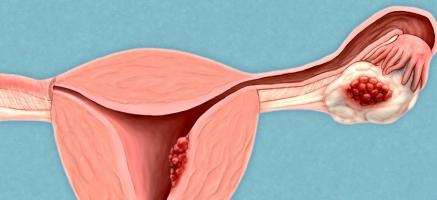

CANCER de l’OVAIRE : Découverte d’un gène régulateur majeur

Actualité publiée le 06/04/2025CANCER de l’OVAIRE : Ovaprint, le test sanguin de détection précoce

OVAIRES POLYKYSTIQUES : Le risque de cancer double après la ménopause

Actualité publiée le 25/07/2023CANCER de l’OVAIRE : Les promesses des conjugués anticorps-médicament

CANCER de l’OVAIRE : Le détecter à l’échographie ?

Actualité publiée le 21/04/2022CANCER de l’OVAIRE : Comprendre l’interaction cruciale entre le sang et la tumeur

CANCER de l’OVAIRE : Un nouveau test sanguin pour le diagnostiquer

Actualité publiée le 12/08/2019CANCER de l’OVAIRE : Pousser les cellules cancéreuses à la sénescence

CANCER de l’OVAIRE : Enfin l’espoir d’un test de détection précoce !

Actualité publiée le 23/03/2018CANCER de l’OVAIRE : Un nouveau gène de risque transmis via l'X par le père